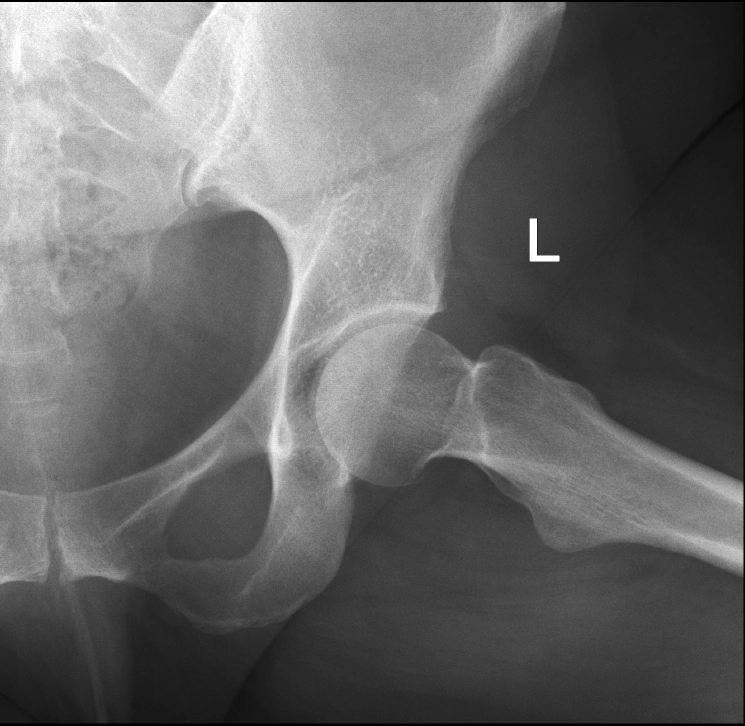

Некроз тазобедренного сустава: Фотографии и особенности лечения